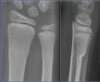

What sort of fracture is this?

Buckle fracture: no breach of cortex

Only requires a splint